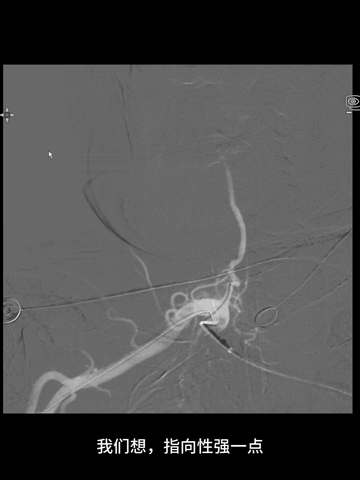

穿刺右桡动脉,置入6F桡鞘;4F长多功能管(125cm)和Navien 072(105cm)组成同轴,泥鳅导丝导引下,4F管头端行至右锁骨下动脉近端。

经4F管送入先前的微导管微导丝,微导丝顺利通过右V1曲折,跟进微导管过程中,支撑不足,弹回右锁骨下动脉。

调整4F头端位置和方向,经数次尝试后,微导丝再次进入右椎动脉,并克服V1曲折上高到V3。

后续微导管顺利跟进到V3,撤出Command 14导丝,送入0.18"导丝(Commmand 18)导丝增强支撑,此时中间管沿微导管微导丝推送到V3。

中间管被进一步推高到V4近端。